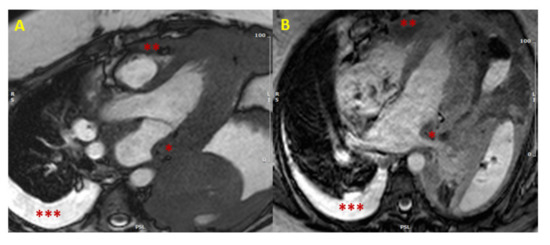

- Moscatelli, S.; Nardi, B.; Indolfi, E.; Fazzari, F.; Montini, O.; Coppini, L.; Monti, L. P586An unusual phenocopy of hypertrophic cardiomyopathy: A case report. Eur. Heart J. Cardiovasc. Imaging 2019, 20, 586. [Google Scholar] [CrossRef]